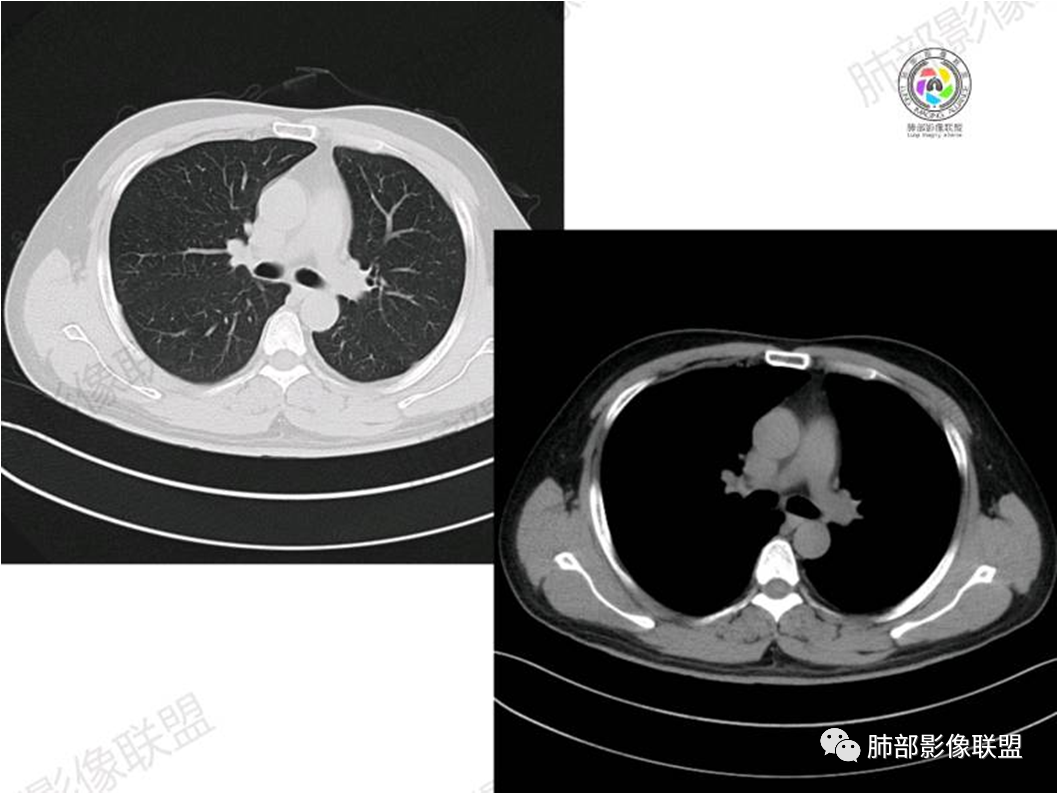

胸部CT:

中年男性,偶有咳嗽,右肺上叶近纵膈旁占位,内可见僵硬的支气管和小空泡征,病灶边缘可见分叶,毛刺,增强病灶中度以上不均匀强化,可见血管造影征,考虑恶性病变,腺癌可能性大。

中年男性,右肺上叶尖段团片病灶,密度均匀,内部支气管充气相,渐进狭窄,强化均匀,血管造影,纵隔侧未见侵犯,诊断:良性,慢性非特异性炎症/机化性炎症,IMT

右肺上叶纵隔胸膜侧一实性肿块,与纵隔胸膜宽基底相连,局部脂肪间隙消失,形态欠规则,内部可见多个小空泡,平扫密度尚均匀,增强后可见点条状强化,内部穿行血管,周围肺组织干净,纵隔淋巴结略肿大,男性44岁,只有咳嗽,考虑恶性肿瘤,腺癌,鳞癌。鉴别结核,OP,炎性假瘤。

右肺上叶近纵膈旁肿块,密度均匀,边缘分叶,毛刺,气管受压变窄,不均匀强化,可见血管造影征,考虑淋巴瘤,鉴别炎性假瘤。

中年男性,右肺上叶纵隔旁软组织肿块,边缘膨隆、毛糙,可见多发分叶,支气管穿行,部分截断,增强后密度欠均匀,纵隔内见多发小淋巴结,首先考虑恶性,腺癌,鉴别淋巴瘤

中年男性,右肺上叶纵隔旁肿瘤,稍膨隆,有毛刺,支气管穿行,远端闭塞,强化均匀,血管走行尚可,考虑淋巴瘤可能性大(支气管远端闭塞,不太符合),鉴别腺癌(气管穿行后闭塞,不太符合),op(病灶稍膨隆)

患者中年男性,咳嗽就诊,无其他不适。胸部CT:右肺上叶尖段上纵膈旁肿块,边界清楚,边缘光滑,内见支气管受压变窄,伴阻塞性改变,增强均匀强化,见血管造影征。综合考虑恶性病变,小细胞肺癌或淋巴瘤。气管镜活检应能明确。

中年男性,右肺上叶纵隔旁实性病灶,边缘有彭隆,有平直,有分叶,有尖角,病灶边缘中心可见支气管征,周围少许磨玻璃,边缘模糊,增强后动脉期病灶可见强化血管影,渐进性强化,临近血管界限清晰。考虑炎性病灶,普通炎性肉芽肿?结核?炎性肌纤维母细胞瘤?鉴别腺癌,淋巴瘤